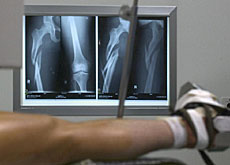

Scientists created a space around the rabbits’ healthy tibia – in humans the inner and larger of the two bones of the lower leg, extending from the knee to the ankle.

Replacement bone is required in cases of serious fractures or diseases such as cancer, when bone is destroyed.

The current technique for dealing with serious fractures or bone diseases involves breaking bone from the rib or hip and can be very painful. There is also the risk of rejection after a transplant.